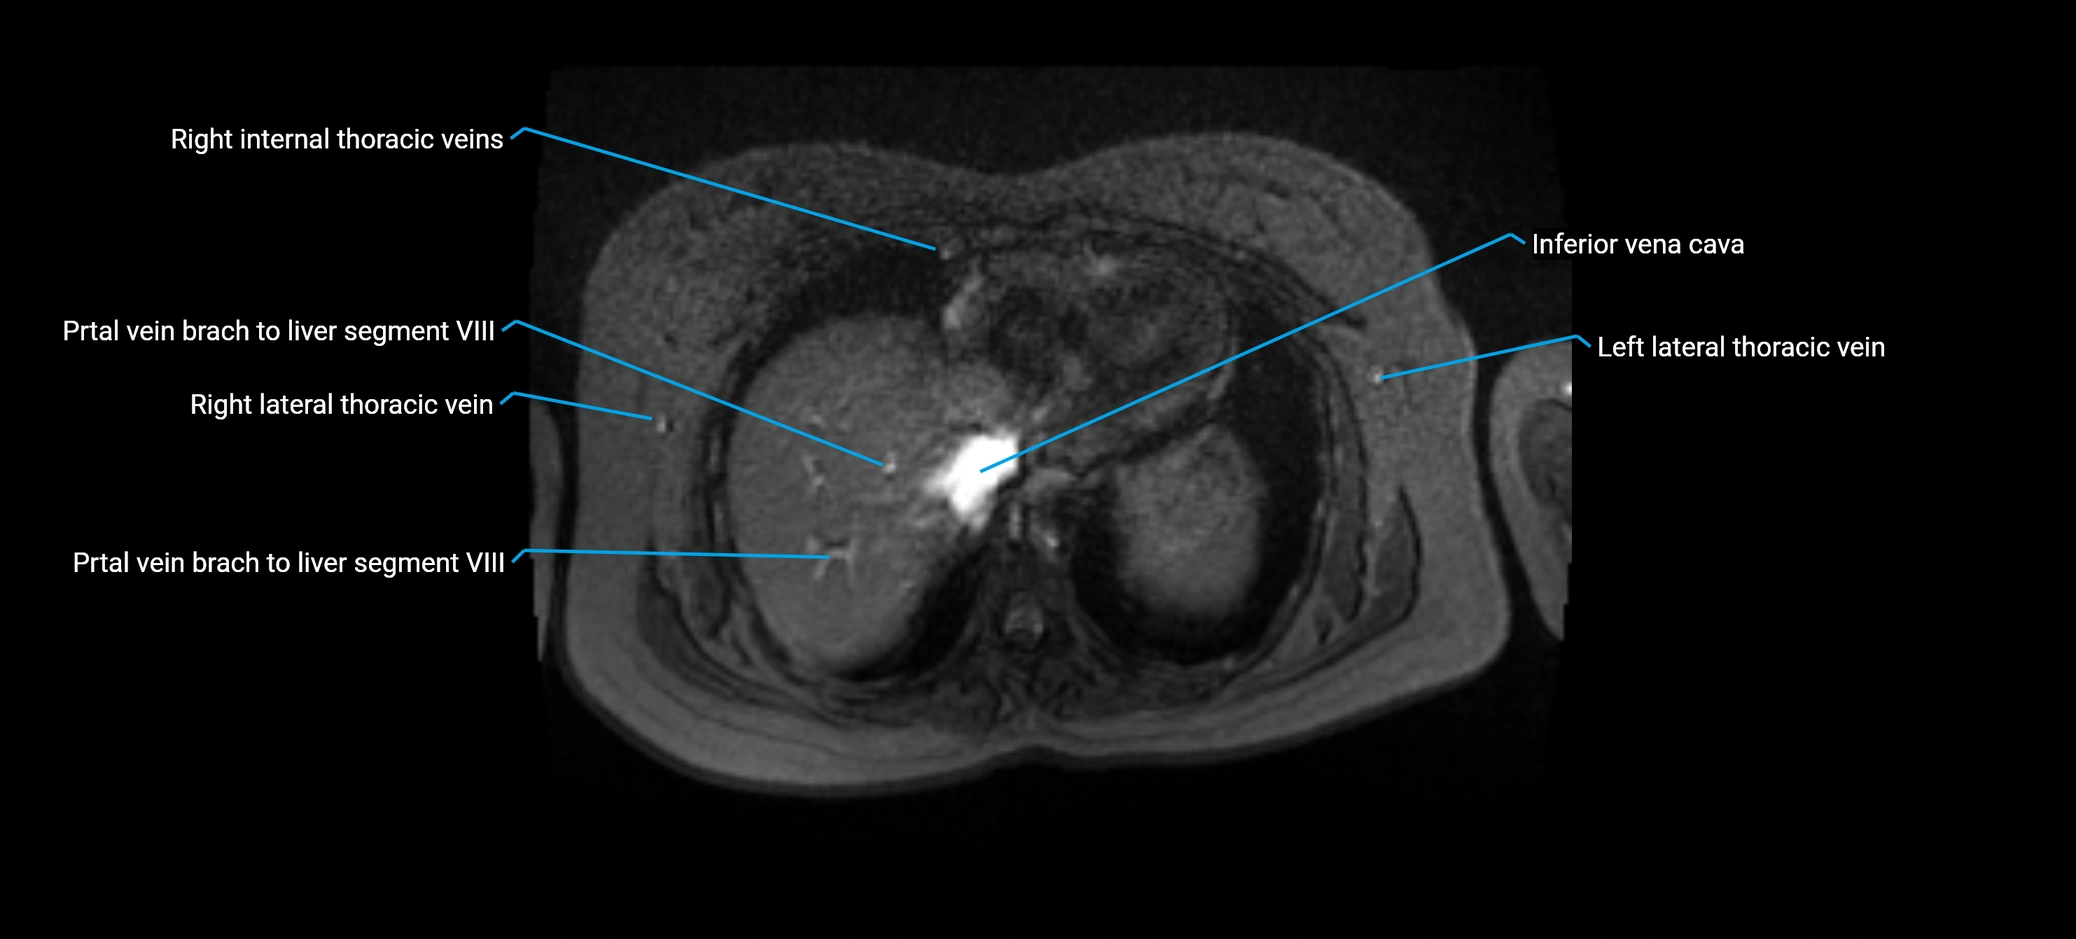

MRV TOF (Time-of-Flight MR Venography):

• Appears as a bright, high-signal vascular channel representing flowing blood

• Clearly shows branching pattern of right portal vein into anterior and posterior branches

• Best in coronal or axial reconstructions for segmental mapping

• No need for contrast, relies on flow-related enhancement

Post-Contrast T1 Fat-Sat GRE:

• Enhances brightly and homogeneously during the portal venous phase

• Clearly delineates branching into segments V and VIII

• Best sequence for evaluating patency, caliber, and anatomic variants

MRI image

image